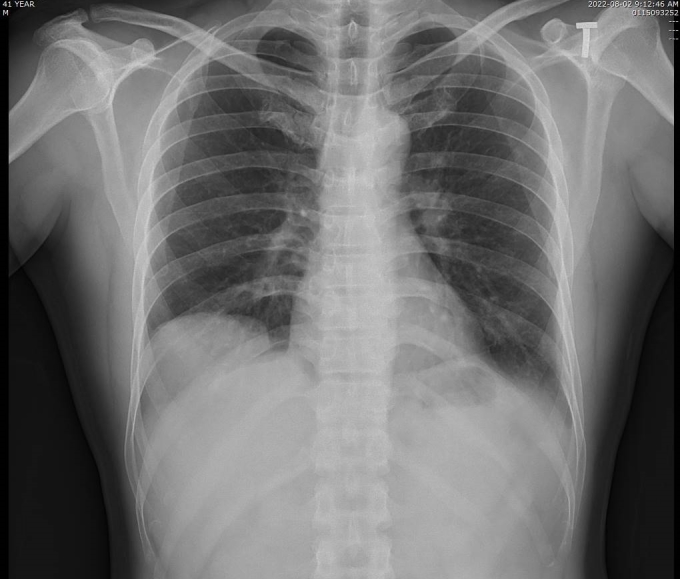

Hình ảnh X-quang phổi của bệnh nhân bị nhão cơ hoành khiến tạng dưới ổ bụng di chuyển lên trên gây xẹp thùy dưới phổi phải. Ảnh: Bệnh viện cung cấp

Phát hiện bệnh hiếm sau nhiều ngày ho, khó thở. Một người đàn ông 42 tuổi ở Quảng Nnh ho nhiều, khó thở, cơn đau tăng lên khi nằm ngửa, bác sĩ khám phát hiện bị nhão cơ hoành - một bệnh hiếm gặp.

Kết quả chụp cắt lớp vi tính tại Bệnh viện đa khoa tỉnh Quảng Ninh cho thấy vòm hoành phải của bệnh nhân cao, gan di chuyển lên trên gây xẹp thụ động nhu mô phổi lân cận. Bác sĩ chẩn đoán bệnh nhân bị nhão cơ hoành phải, chỉ định phẫu thuật nội soi tạo hình cơ hoành.

Bác sĩ cho biết nhão cơ hoành là bệnh lý hiếm gặp, khó phát hiện và dễ bị chẩn đoán nhầm với các bệnh khác, như nang thùy dưới phổi, viêm phổi, bệnh phổi biệt lập... do các triệu chứng không đặc trưng, thường phát hiện tình cờ khi chụp X-quang phổi.